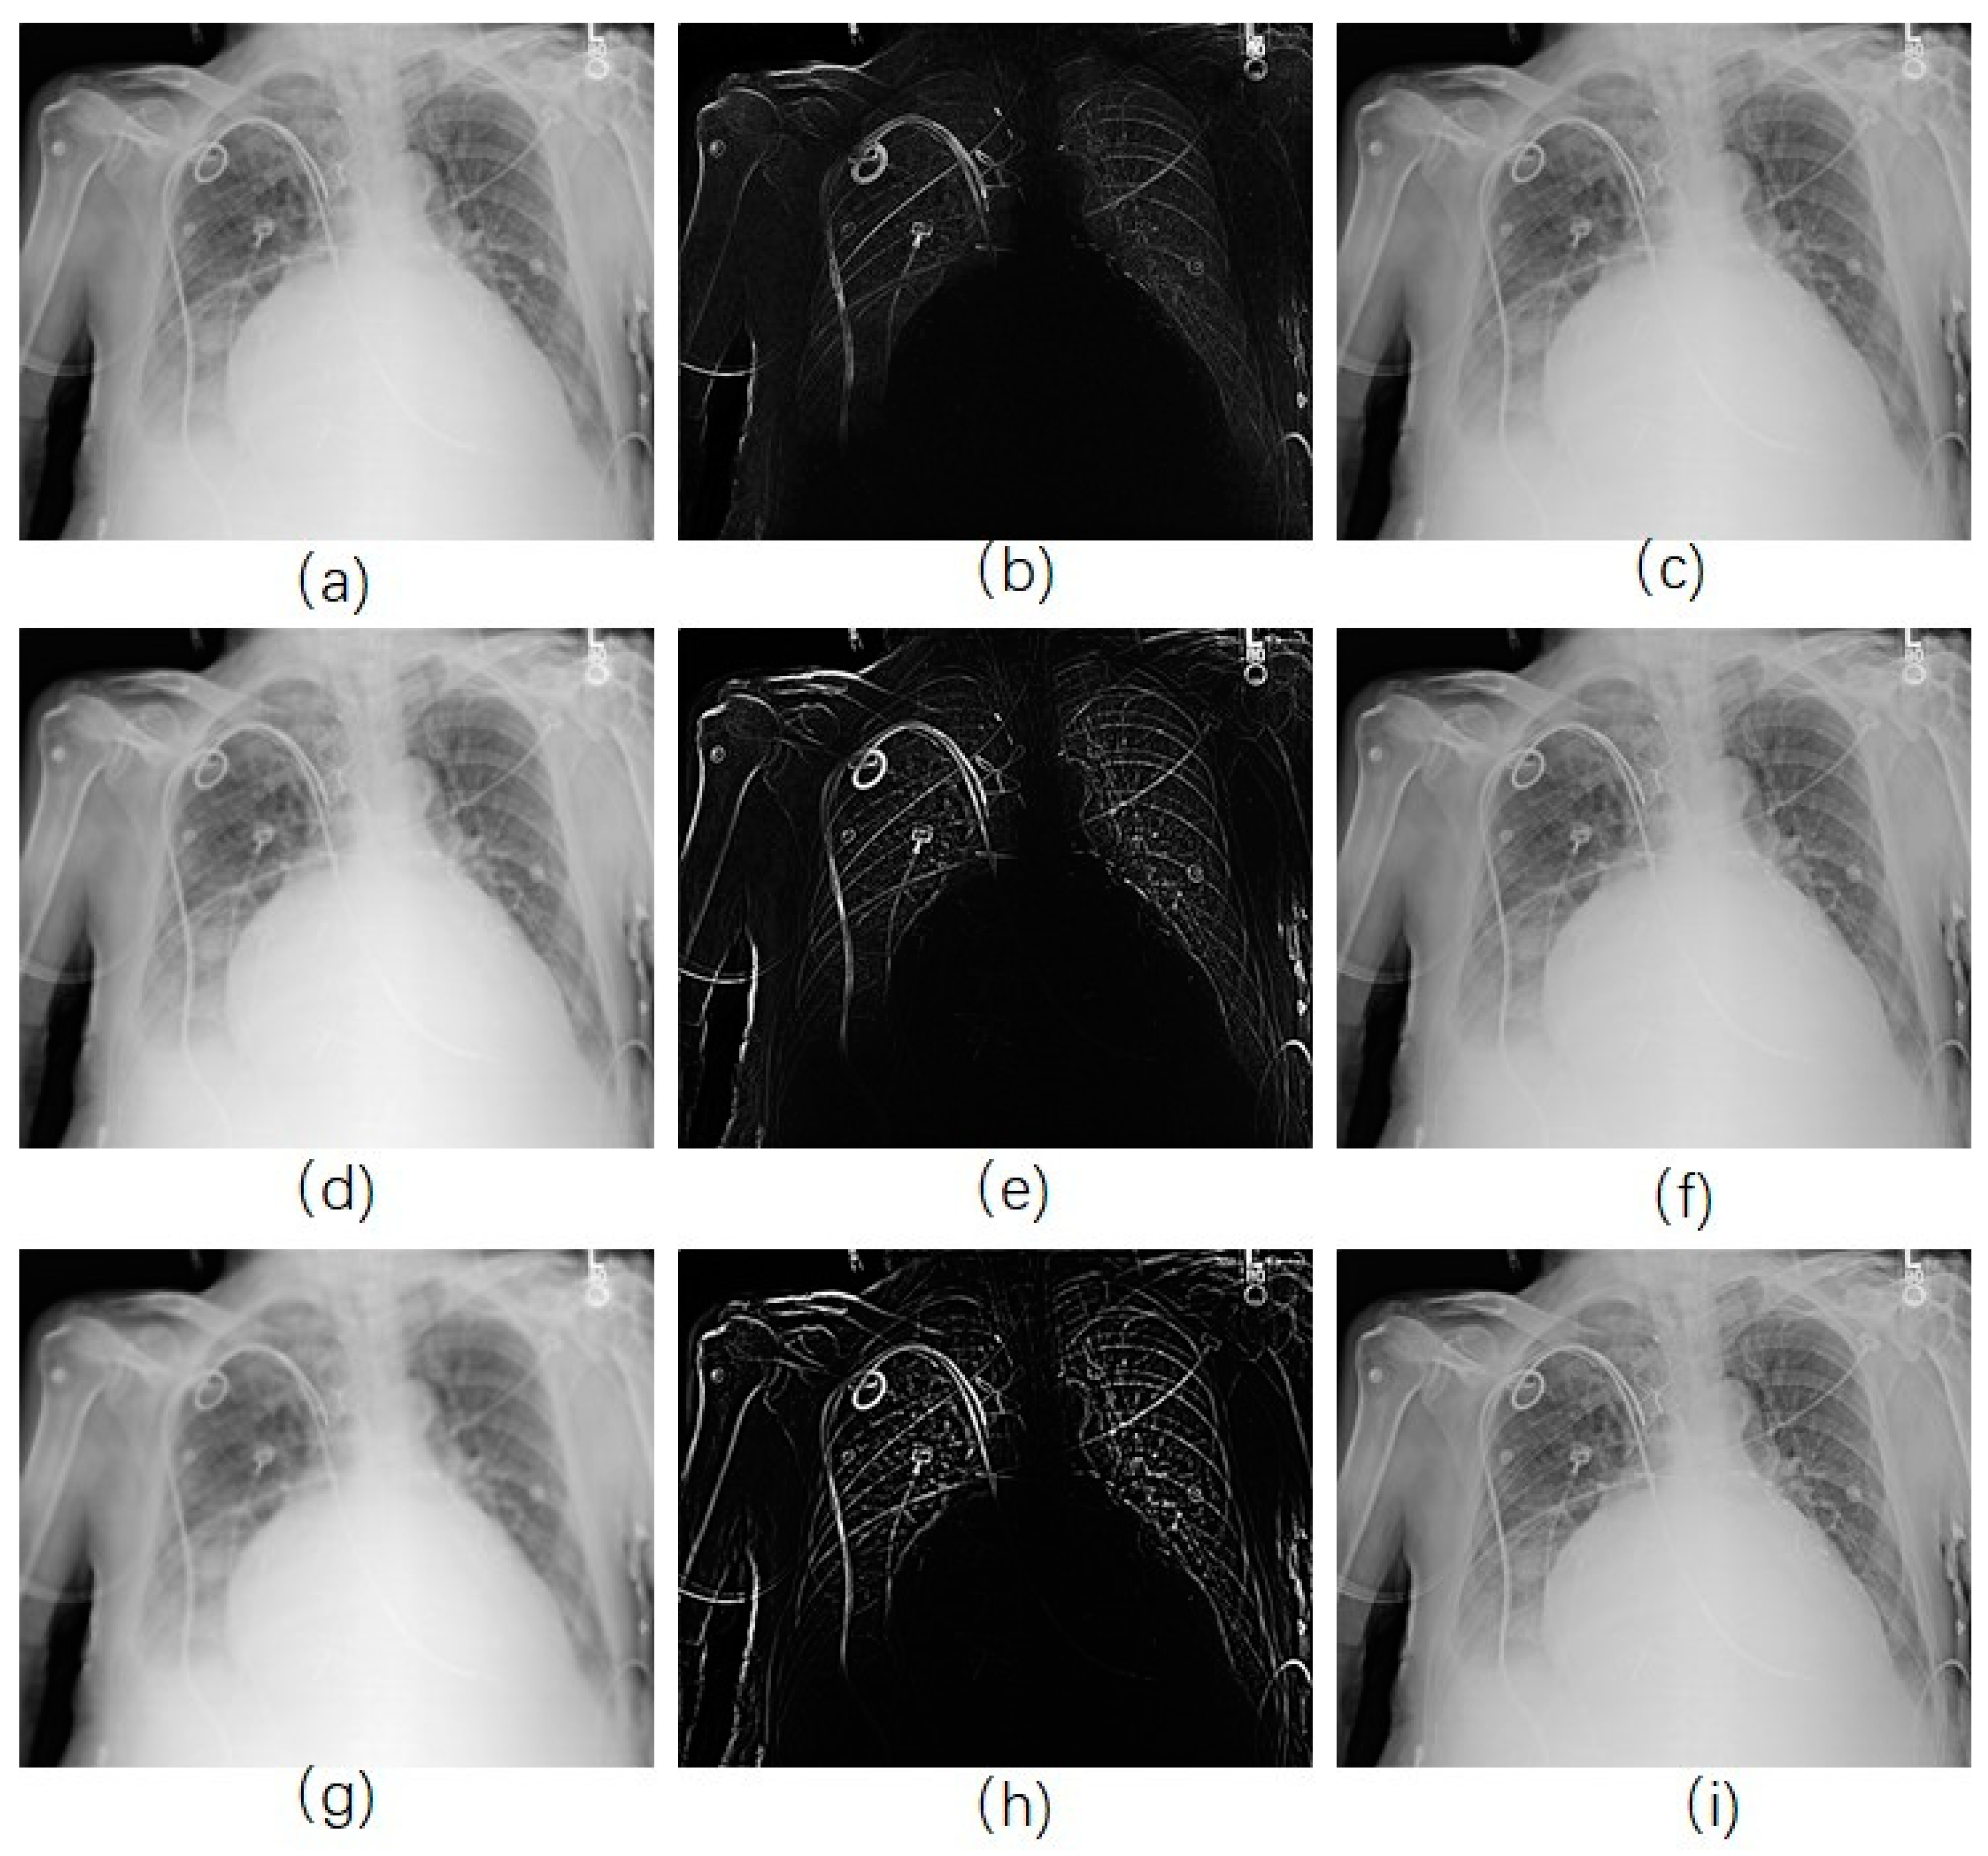

In the RAD-based USM method, the parameter α dramatically influences the result. Several different values for this parameter were set so that we can analyze the effect of this term according to various parameters. Firstly, we started with a very small value of 0.001. As we can see in Figure 5a–c (EMEE = 0.587), the result was not desirable since there was the presence of noise. In addition, it did not show a clear contour. As we magnified the parameter α , the result was improved. As α approached approximately 0.02, the EMEE value of the result was 1.24 (Figure 5d–f), which was greater than that for the traditional method. The noise was less than that shown in Figure 4 and the contour was clearer. When the parameter α became bigger, for example, 0.2 (Figure 5g–i), the EMEE value was 1.43, which was greater than the EMEE value for α equal to 0.02. More structural information was enhanced in the unsharp mask (Figure 5h). Indeed, we have observed that the contours became thicker. The edge of the ribs became wider which was a good outcome. It was also noticed that less noise was presented in the unsharp mask. The reason for this phonomenon is that the diffusion is too strong. We set α with 0.02 and applied our RAD-based USM method for each CXR in the portable CXRs database. Then, we calculated EMEE values for every CXR. To facilitate a comparison, we also calculated the EMEE values for every CXR by using the traditional USM method for the portable CXRs database. Figure 6 shows that the RAD-based USM method usually has a larger EMEE value than that the Gaussian filter-based USM method has. Objective and subjective evaluation methods show that the proposed method is acceptable.

Figure 5. CXR enhancement by use of reverse anisotropic diffusion (RAD) -based USM. (a,d,g) were the smoothed images with diffusion parameter 0.001, 0.02, 0.2, respectively; (b,e,h) were the corresponding unsharp masks to (a,d,g); (c,f,i) were the corresponding enhanced images.